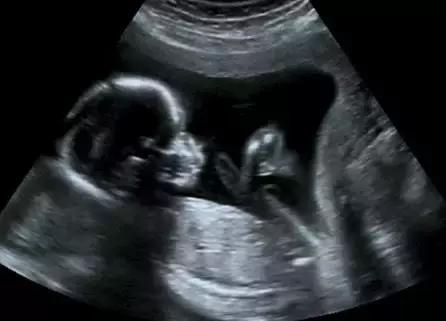

- 看双顶径和股骨长 -

双顶径即胎儿的头部横直径,而股骨长则是胎儿的大腿骨长度,老一辈们的说法是,头大腿短的是男孩,即双顶径-股骨长>2,头和腿相差小的是女孩。